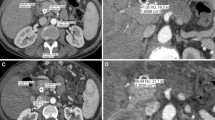

Table 5 and Fig. 3 provide results of subjective image quality evaluation. According to two readers, the median rating of overall image quality was 2 (good) in both groups; however, difference of ratings between groups reached significance towards a higher image quality in group A (p = 0.035). In detail, examinations in group A were exclusively rated as 1 (n = 13/33) or 2 (n = 20/33), whereas ratings in group B were 1 in 6/27, 2 in 16/27, and 3 in 5/27 examinations. Of the five patients in whom the image quality was rated 3, the mean BMI was 44 kg/m2. For both groups, no minor or major motion artifacts were documented.

Figures (A,B) illustrate a high-pitch portal-venous abdominal CT of a 59-year old female patient with acute pain in the upper abdomen (BMI 31 kg/m2, AP + LAT 70 cm; CTDIvol 6.38 mGy, SSDE 6.64 mGy, DLP40cm 222 mGy * cm, ED40cm 3.77 mSv; (A), transversal; (B), coronal), showing both slight swelling of the pancreatic head (*) and diffuse stranding of the adjacent mesenteric fat (arrows). Marked elevation of serum lipase confirmed the suspected diagnosis of acute pancreatitis. Image quality was rated ‚excellent‘. (C,D) show a high-pitch portal-venous abdominal CT of a 41-year old female patient with history of leiomyosarcoma and acute persistent pain in the left lower abdomen (BMI 41 kg/m2, AP + LAT 81 cm; CTDIvol 14.13 mGy, SSDE 12.15 mGy, DLP40cm 587 mGy * cm, ED40cm 10.00 mSv; (C), transversal; (D), coronal). In this CT examination, an extraabdominal mass adjacent to the abdominal muscles on the left was diagnosed, in the sense of an abdominal wall metastasis (arrows in D). The contrast-enhancing tumor had a well-defined morphology, semi-liquid components, and yielded diffuse stranding of the adjacent fatty tissue. The abdominal muscles (* in D) were slightly translocated due to the mass effect, but sharply definable without signs of tumor infiltration. The image quality was rated ‚good‘ in this patient. Figures (E,F) show a high-pitch portal-venous abdominal CT of a 35-year old male patient with acute pain in the right upper abdomen (BMI 47 kg/m2, AP + LAT 86 cm; CTDIvol 17.34 mGy, SSDE 13.53 mGy, DLP40cm 720 mGy * cm, ED40cm 12.24 mSv) (E), transversal; (F), coronal). The CT scan revealed no pathology, particularly no signs of cholecystitis. Overall image quality was rated ‘good’.